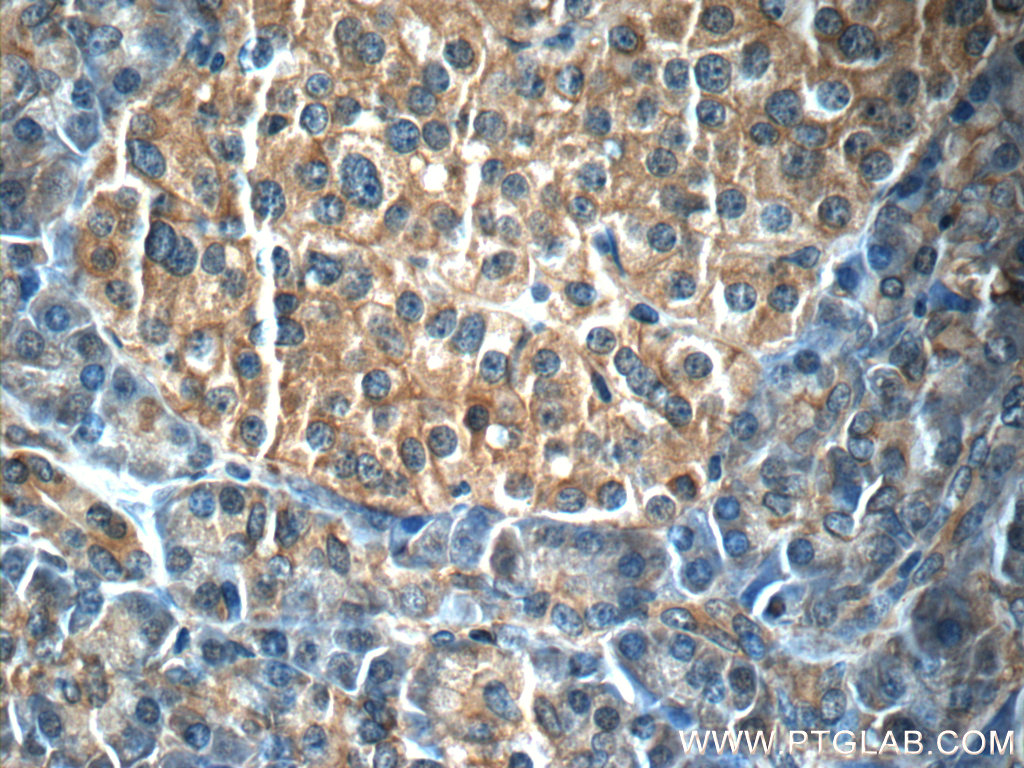

| Positive IHC detected in | human stomach cancer tissue, human pancreas tissue Note: suggested antigen retrieval with TE buffer pH 9.0; (*) Alternatively, antigen retrieval may be performed with citrate buffer pH 6.0 |

| Immunohistochemistry (IHC) | IHC : 1:50-1:500 |

66196-1-Ig targets IL-23 p19 in WB, IHC, IF, ELISA applications and shows reactivity with human samples.

| 经测试应用 | IHC, ELISA Application Description |